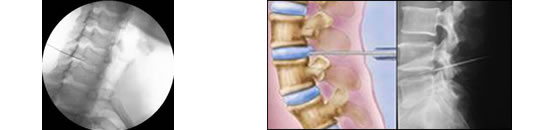

Discólisis Percutánea

Se basa en la inyección de una mezcla de ozono con oxígeno directamente en un disco intervertebral herniado bajo control radiológico, generando

así la deshidratación del núcleo pulposo discal por la degradación de los proteoglicanos que forman parte del mismo; y reduciendo así su volumen.

Este procedimiento se realiza en quirófano, bajo estrictas condiciones de asepsia, con anestesia local y sedación. En algunos casos se combina

con un bloqueo radicular o facetario del nivel a tratar. No requiere internación. El paciente permanecerá aproximadamente 2hs en observación luego

del procedimiento. Es un procedimiento altamente efectivo y seguro.